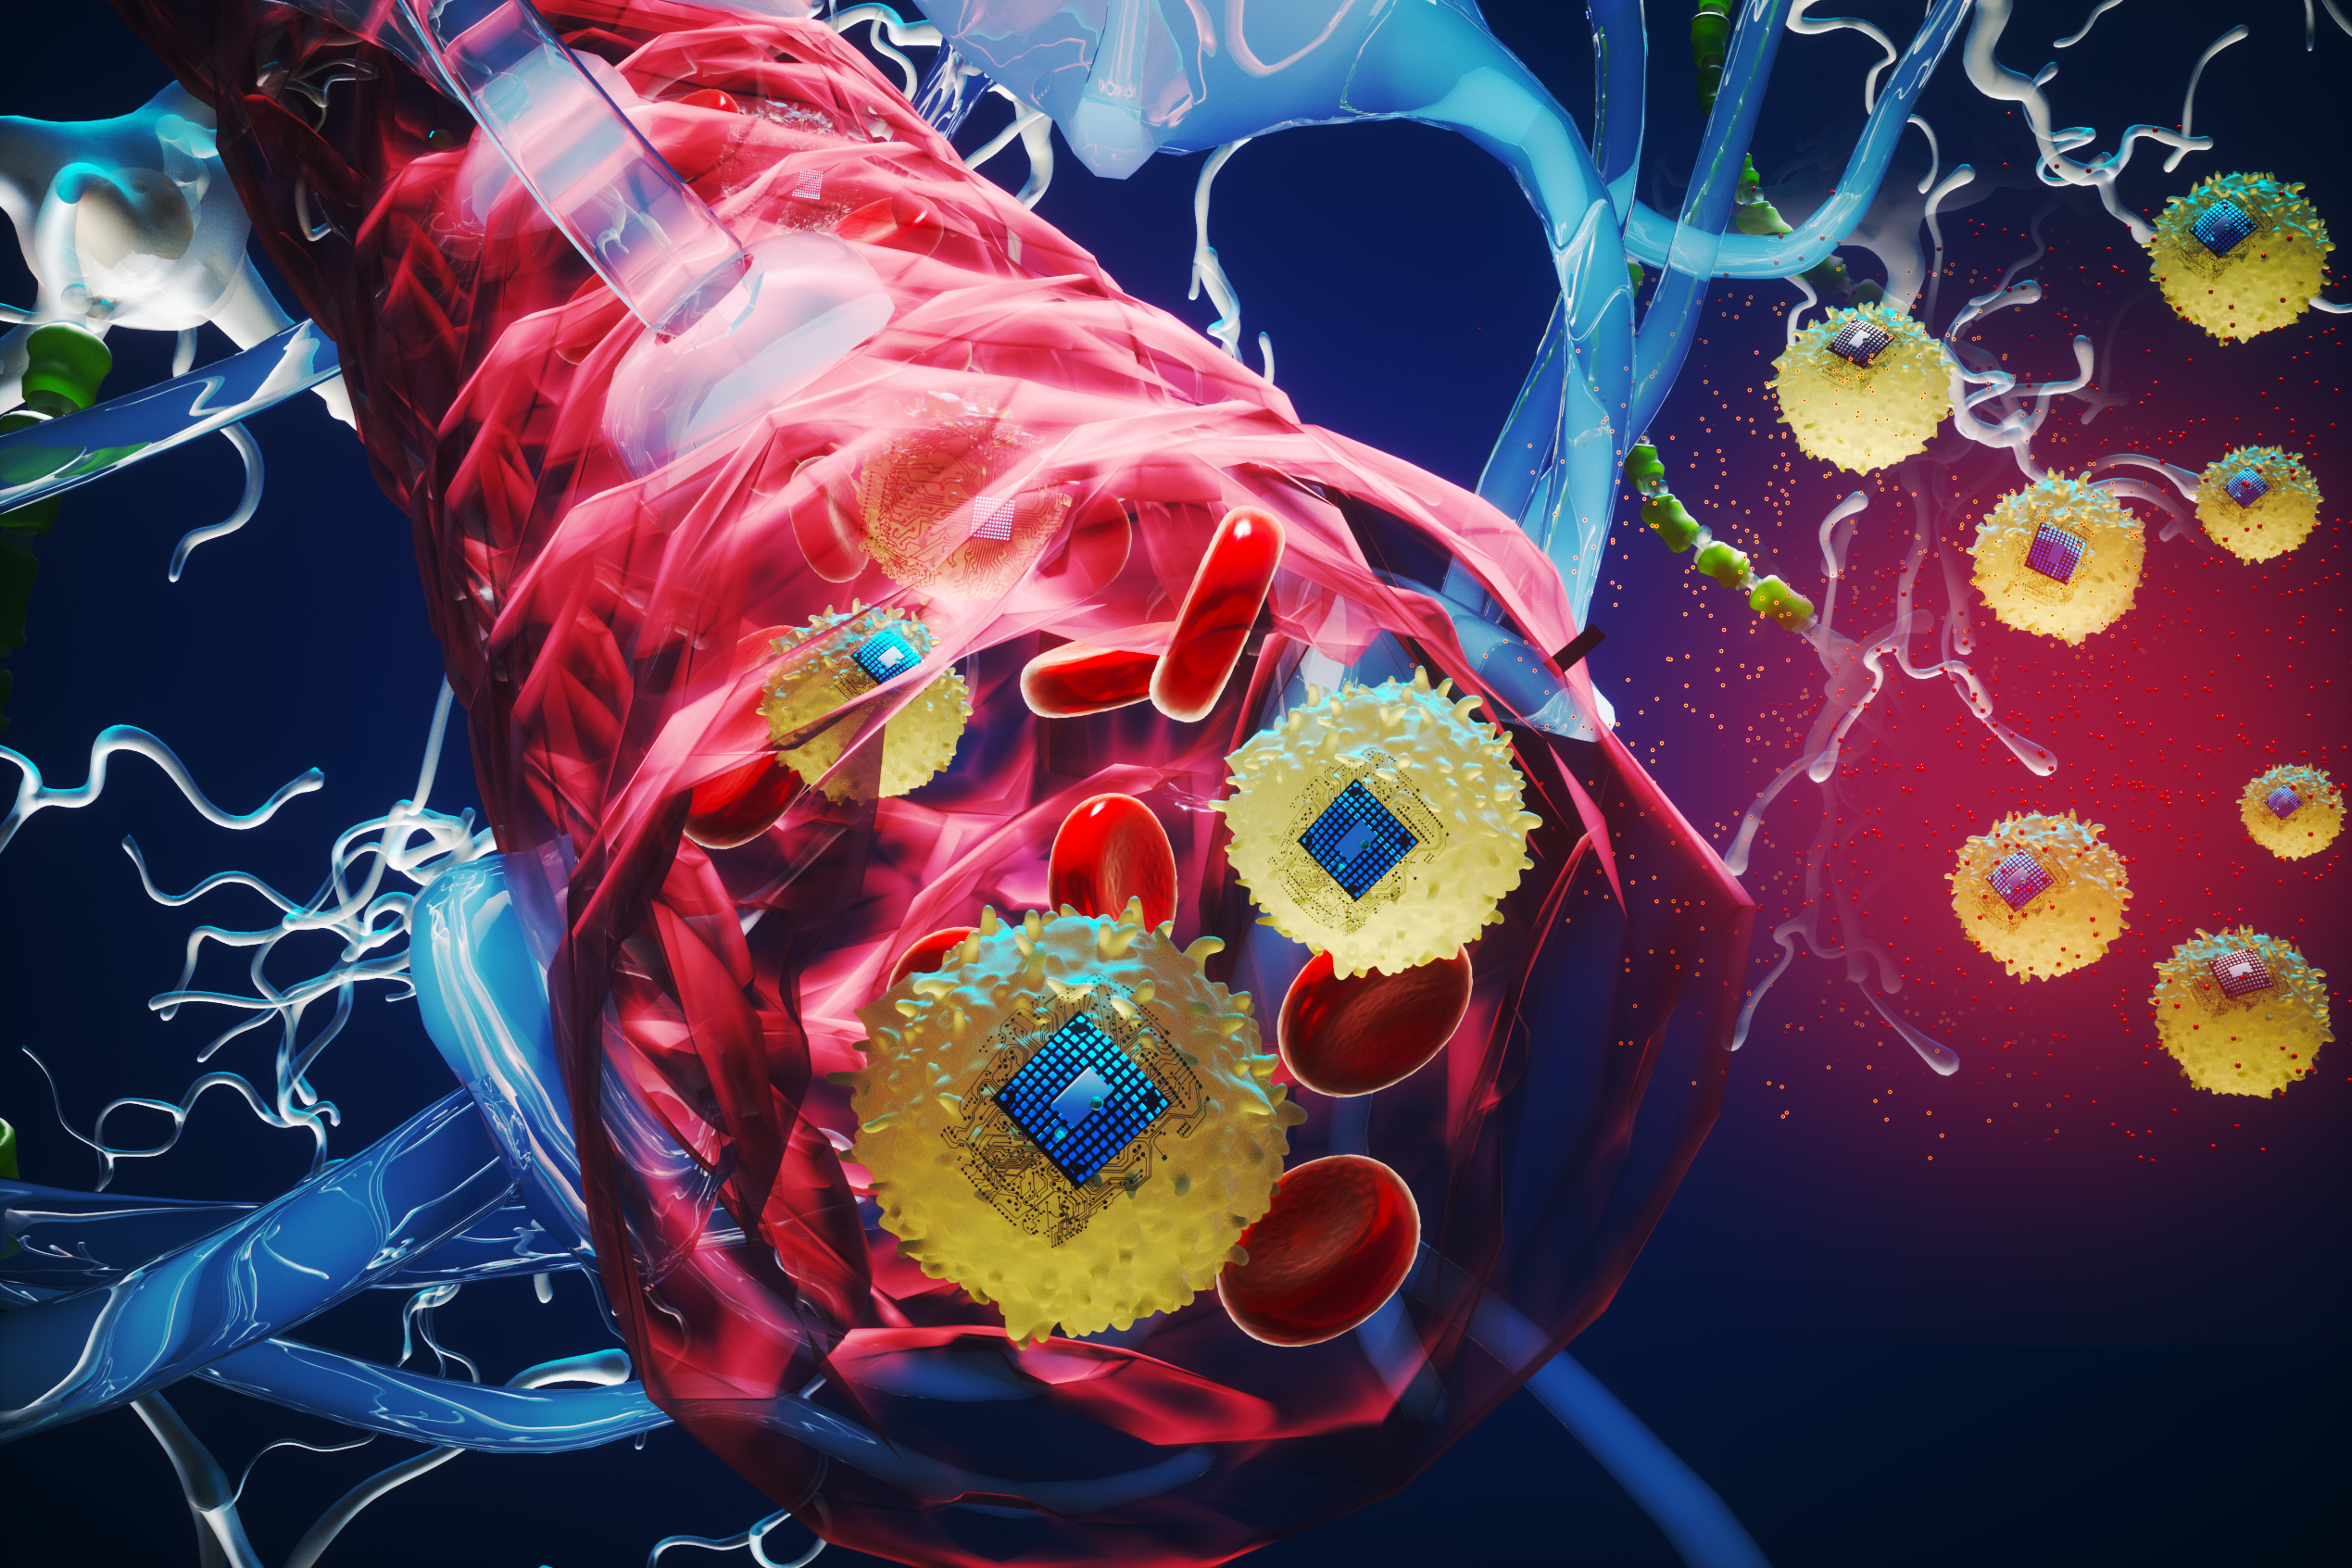

- New therapeutic brain implants could defy the need for surgeryMIT researchers created microscopic wireless electronic devices that travel through blood and implant in target brain regions, where they provide electrical stimulation.